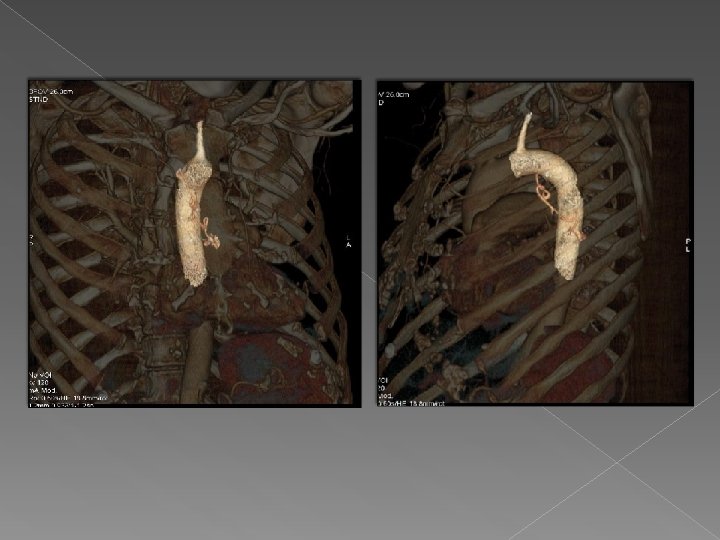

Valor de VR : se visualiza la arteria aferente que se origina en

Valor de VR : se visualiza la arteria aferente que se origina en la aorta y se dirige a la masa con un drenaje venoso a la vena pulmonar inferior derecha. Hallazgos sugestivos de secuestro pulmonar intralobar.

Drenaje venoso Secuestro pulmonar